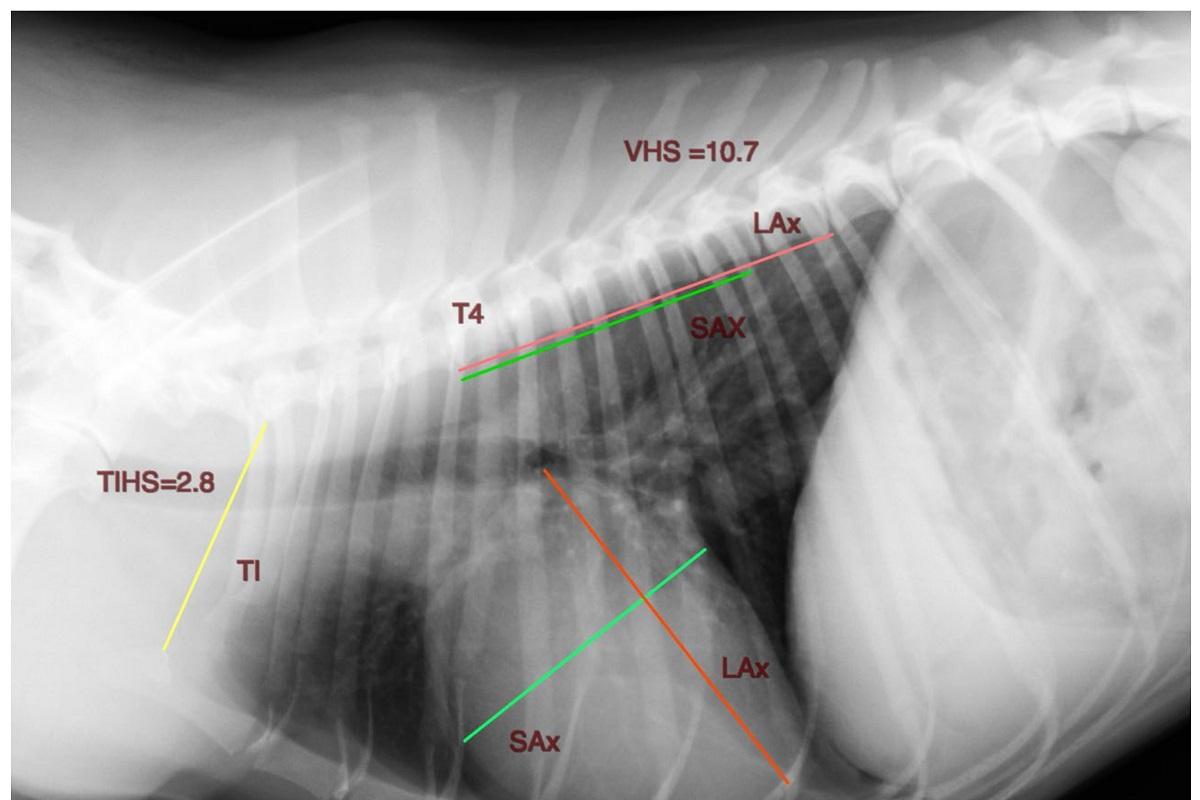

Por ello, un estudio publicado en la revista internacional Animals(1) en el que ha participado AniCura Albea Hospital Veterinario, centro especializado en cardiología, entre otras disciplinas, describe un nuevo método radiográfico conocido como TIHS, que evalúa el tamaño del corazón del perro con respecto al tamaño corporal utilizando la longitud de la entrada torácica. De este modo, y mediante una proyección torácica lateral derecha, se podrían identificar fácilmente perros que presentasen cardiomegalia.

"A todos los perros analizados se les realizó un estudio ecocardiográfico para valorar las dimensiones del ventrículo y del atrio izquierdo, así como una proyección radiográfica torácica lateral derecha. A la mayoría de los pacientes también se les tomó una proyección ventrodorsal lateral izquierda", explica David Marbella, autor principal del estudio e integrante del Área de Cardiología y Cirugía Cardiovascular del centro. "La longitud de la entrada torácica la definimos como la distancia más corta medida entre el borde craneodorsal del manubrio esternal, en su punto más alto, y el borde craneoventral del cuerpo de la primera vértebra torácica", añade.

Tras analizar los resultados, se concluyó que el TIHS es un método sencillo, directo, fiable y reproducible para medir la silueta cardíaca de un perro en una proyección torácica lateral derecha. Con un valor medio de 2,86 y un intervalo de confianza de 2,81-2,91 (95%), se sugiere un valor TIHS ≤ 3,2 como límite superior para definir el tamaño normal del corazón de un perro sano.